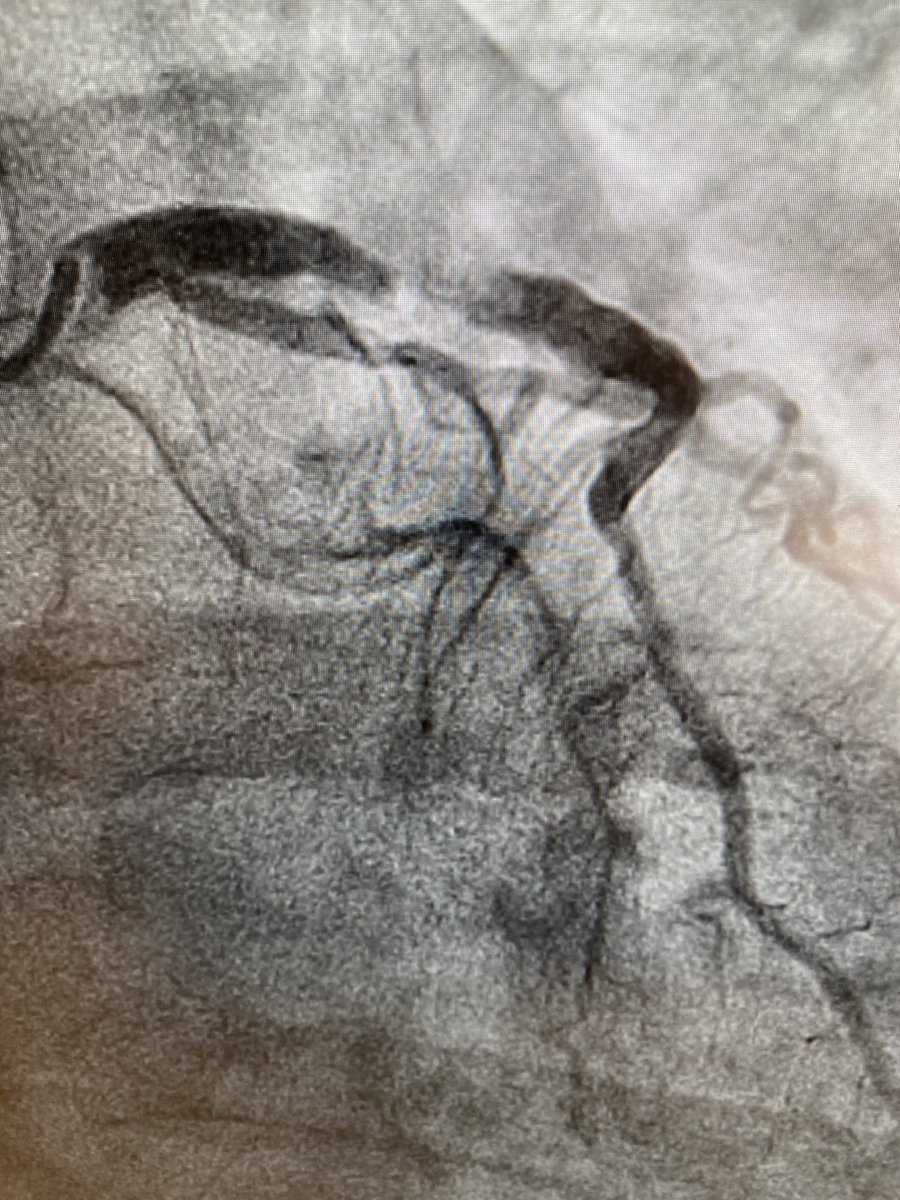

50yo nonDM👨🏻🦳 2+mo exertional angina, Trop/echo WNL. How would you manage? #CardioTwitter 🎥 on RP @mmamas1973 @SandeepNathanMD @mirvatalasnag @djc795 @SVRaoMD @rajivxgulati @Drroxmehran @DLBHATTMD @djkereiakes @BinitaShahMD @CardioNerds @DrJayMohan @richardbogle @fischman_david